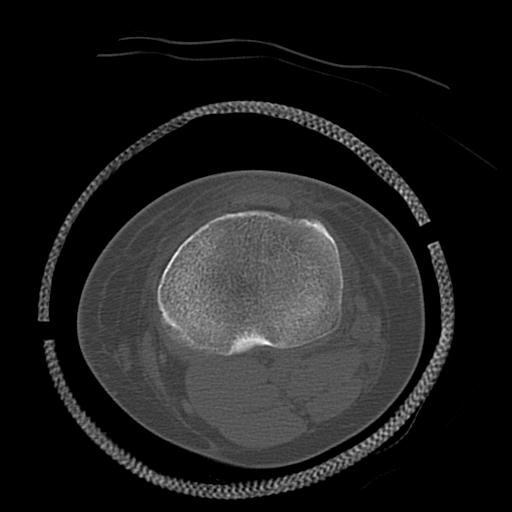

49554 3/13 膝 4R 3/16 4R 1/18 2R 78歳男性 膝蓋骨骨折